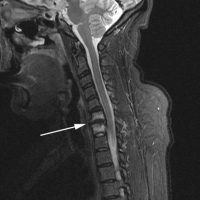

(Click to Enlarge Image) IDR of C6-7. Note the loss of disc height, white signal of the vertebral bodies. Small arrow points to endplate fracture.

The MRI findings of isolated disc resorption (IDR) are classic. First, the disc will be very narrowed and have lost most of its original height. The disc space will appear black due to the loss of water from the nucleus and then loss of the nucleus itself.

The cortical endplates of the bone, which are normally uniform and regular, are found to be irregular with small endplate fractures. Some call these “moth-eaten” or “rat-bite” appearances.

The inside or internal body of the vertebra will be whitened along these fractured edges (noted on a T2 image in which water is white). This is due to fluid accumulation from the fractured trabecula, which seeps into this area.